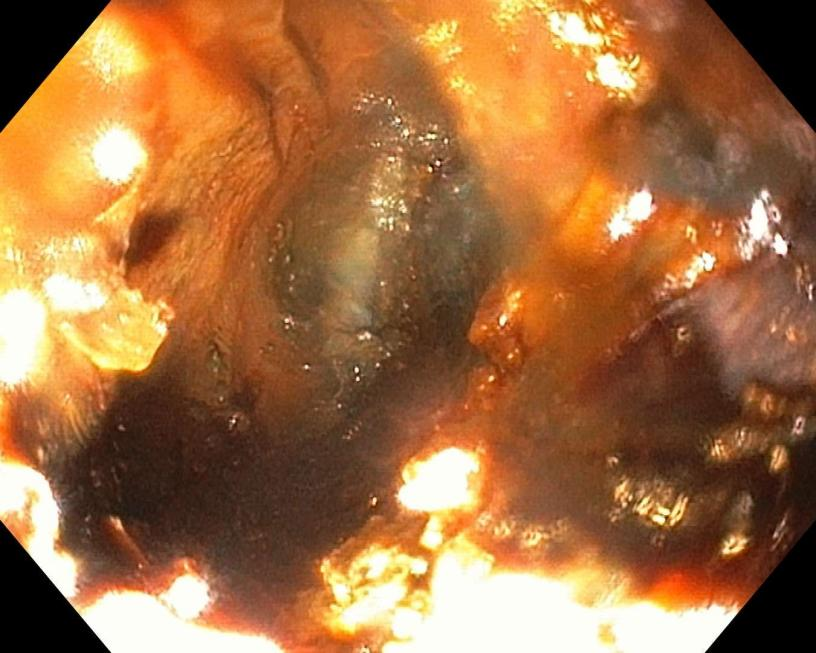

△被电池腐蚀的消化道